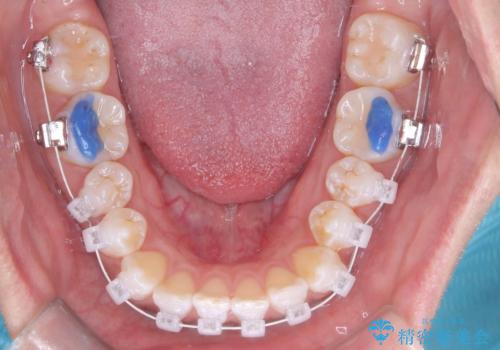

- 矯正歯科治療

- 2012~2025年6月

- 000件

- インビザライン

- 2015~2025年6月

最新の症例

Latest cases